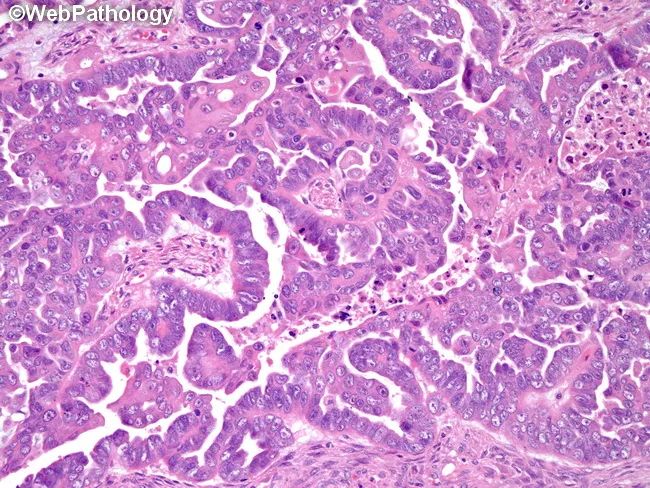

(结构)肿瘤常出现多种生长模式,常见复杂乳头状和实性细胞巢 (巢团常伴狭缝状间隙)[特征],可见:复杂的腺样、筛状、迷路状、裂隙状,肿瘤呈破坏式、浸润性生长[特征],可见砂粒体,常见坏死

(细胞)细胞立方形或多角形,核体积大,重度异型 (核大小变化>3倍),常见多核细胞[特征],核分裂像常见 (通常>12/10HPF)[特征],少见微囊状伴黏液分泌、透明或印戒细胞样、梭形细胞样

WT1、PAX8、CK7阳性 (WT1有助于鉴别卵巢和子宫内膜浆液性癌) ,ER、PR不同程度阳性,P53常显示突变型 (低级别浆液性癌常显示野生型),P16常显示强阳性 (低级别浆液性癌常显示斑片状) ,CK20、CDX2、HNF1β 阴性